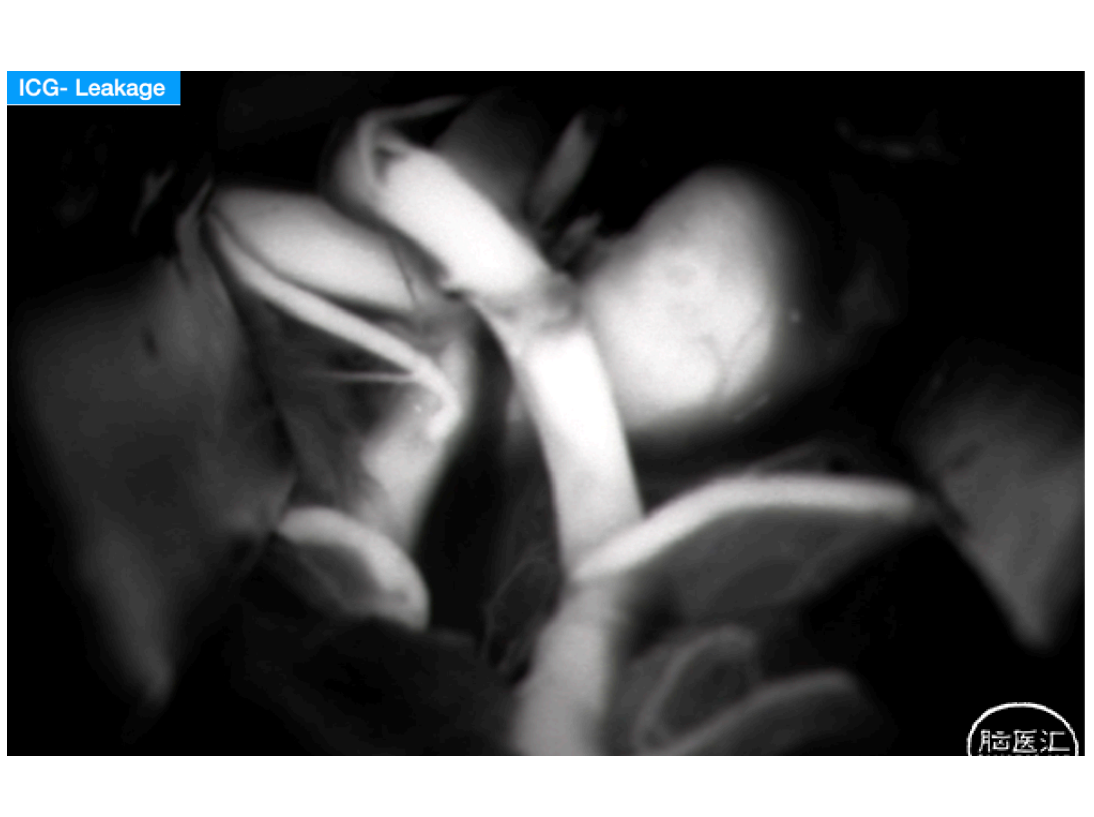

本期脑医汇为大家分享:天津市环湖医院【佟小光教授】的精彩病例内容:纵裂入路-前交通大动脉瘤夹闭术,欢迎阅读和分享!病例视频观看点击图片观看视频讲者:佟小光讲题:纵裂入路-前交通大动脉瘤夹闭术病例内容截图声明:脑医汇旗下神外资讯、神介资讯、神内资讯、脑医咨询、Ai Brain 所发表内容之知识产权为脑医汇及主办方、原作者等相关权利人所有。投稿邮箱:NAOYIHUI@163.com 未经许可,禁止进行转载、摘编、复制、裁切、录制等。经许可授权使用,亦须注明来源。欢迎转发、分享。